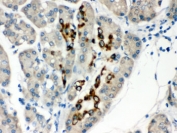

IHC testing of FFPE human pancreatic cancer tissue with PAX6 antibody. HIER: Boil the paraffin sections in pH 6, 10mM citrate buffer for 20 minutes and allow to cool prior to staining.